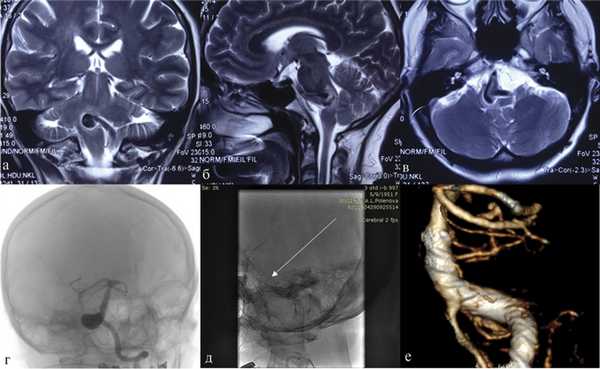

В нашей серии осложнений после имплантации потокоперенаправляющего стента в основную артерию не отмечено (рис. 3). Рис. 3. Фузиформная аневризма правой позвоночной артерии. а, б, в — МРТ головного мозга, коронарная, сагиттальная и аксиальная проекции, режим Т2 В.И. Виден мешок аневризмы, грубо сдавливающий ствол мозга; г — церебральная ангиография в косой проекции; д — церебральная ангиография после установки стента (указано стрелкой); е — контрольная СКТ-АГ через 12 мес. Вместе с тем тромбоз коротких ветвей основной артерии, приведший к гибели пациентки с фузиформной аневризмой основной артерии, развился после имплантации стента. Данное наблюдение свидетельствует о неоднозначности применения стентов у пациентов с аневризмами основной артерии, а также о необходимости индивидуального подхода при выборе тактики лечения пациентов с подобным поражением.